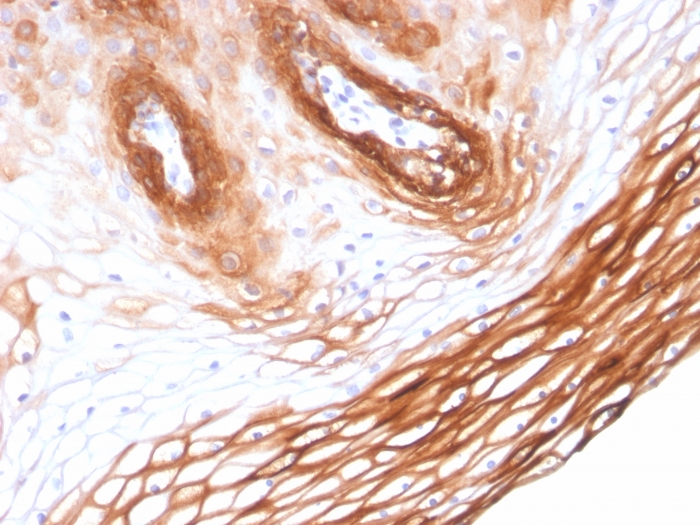

Formalin-fixed, paraffin-embedded human Skin stained with Cytokeratin 14 Mouse Monoclonal Antibody (KRT14/2375).

Cytokeratin 14 (CK14) belongs to the type I (or A or acidic) subfamily of low molecular weight keratins and exists in combination with keratin 5 (type II or B or basic). CK14 is found in basal cells of squamous epithelia, some glandular epithelia, myoepithelium, and mesothelial cells. Anti-CK14 is useful in differentiating squamous cell carcinomas from poorly differentiated epithelial tumors. Anti-CK14 is one of the specific basal markers for distinguishing between basal and non-basal subtypes of breast carcinomas. Anti-CK14 is also a good marker for differentiation of intraductal from invasive salivary duct carcinoma by the positive staining of basal cells surrounding the in-situ neoplasm as well as for differentiation of benign prostate from prostate carcinoma. Furthermore, this antibody has been useful in separating oncocytic tumors of the kidney from its renal mimics, and in identifying metaplastic carcinomas of the breast.